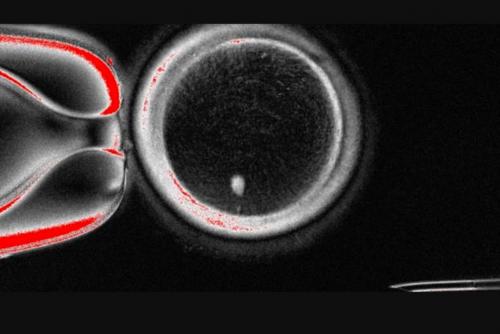

ഒറിഗോണ് ഹെല്ത്ത് ആന്ഡ് സയന്സ് യൂണിവേഴ്സിറ്റിയിലെ ജീവ ശാസ്ത്രജ്ഞനായ ഷൗഖ്രത് മിത്താലിപോവിന്റെ നേതൃത്വത്തിലുള്ള സംഘം നടത്തിയ ഗവേഷണത്തിലാണ് മനുഷ്യചര്മ്മത്തിലെ കോശങ്ങളെ അണ്ഡകോശങ്ങളാക്കി പുനര്നിര്മ്മിച്ച ഈ ഗവേഷണം നടന്നത്. പിന്നീട് ലാബില് വച്ച് വിജയകരമായി ബീജസങ്കലനം നടത്തുകയായിരുന്നു. 'മൈറ്റോമിയോസിസ്' എന്ന് വിളിക്കുന്ന ഒരു പുതിയ പ്രക്രിയയെ അടിസ്ഥാനമാക്കിയാണ് ഈ കണ്ടുപിടുത്തം.

ആദ്യം ചര്മ്മ കോശങ്ങളില് നിന്ന് കോശകേന്ദ്രം (ന്യൂക്ലിയസ്) വേര്തിരിച്ചെടുക്കുകയായിരുന്നു. പിന്നീട് ആരോഗ്യമുളള ദാതാവിന്റെ അണ്ഡത്തിന്റെ ന്യൂക്ലിയസ് നീക്കിയ ശേഷം ചര്മ്മകോശത്തിന്റെ ന്യൂക്ലിയസ് ഈ അണ്ഡത്തില് നിക്ഷേപിക്കുന്നു. 'സൊമാറ്റിക് സെല് ന്യൂക്ലിയര് ട്രാന്സ്ഫര്' എന്നാണ് ഈ പ്രക്രിയ അറിയപ്പെടുന്നത്.

ഈ പ്രക്രിയയിലെ ഏറ്റവും നിര്ണ്ണായകമായ ഘട്ടം ബീജ സങ്കലനത്തിന് 23 ക്രോമസോമുകളുളള ഒരു അണ്ഡം 23 ക്രോമസോമുകള് വഹിക്കുന്ന മറ്റൊരു ബീജവുമായി സംയോജിപ്പിക്കുന്നതാണ്. ഈ രീതി ഉപയോഗിച്ച് ഗവേഷകര് 82 ഫങ്ഷണല് ഓസൈറ്റുകള്(അണ്ഡങ്ങള്) ഉത്പാദിപ്പിക്കുകയും ബീജം ഉപയോഗിച്ച് അവയെ ബീജ സങ്കലനം ചെയ്യുകയും ചെയ്തു. ആറാം ദിവസത്തോടെ ഒന്പത് ശതമാനം ഭ്രൂണവികാസം സംഭവിക്കുകയായിരുന്നു. ഈ പഠനം ശൈശവ ദിശയിലാണ്. എന്നാൽ ആളുകളില് സുരക്ഷിതവും ഫലപ്രദവുമാകുമോ എന്ന് സ്ഥാപിച്ചെടുക്കാന് വര്ഷങ്ങളുടെ ഗവേഷണം അനിവാര്യമാണെന്നാണ് ഗവേഷകർ പറയുന്നത്.